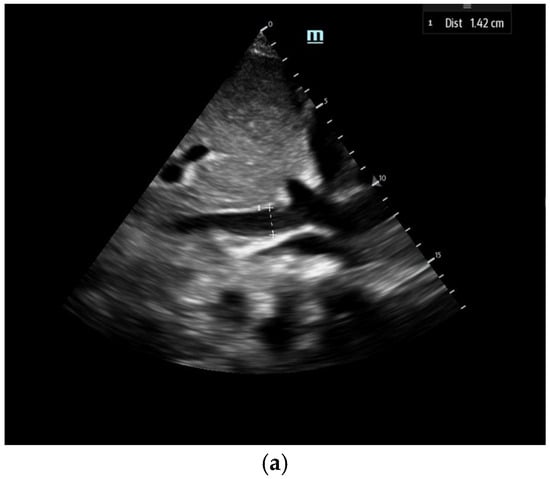

1. Inferior vena cava assessment: The ultrasound assessment of IVC size and collapsibility offers a non-invasive method to evaluate CVP and RAP (Figure 2). The IVC’s diameter varies with CVP and intravascular volume, although factors like positioning, respiratory variation, and intrathoracic pressure may also influence IVC size [17]. Studies show a strong correlation between maximum IVC diameter (IVCmax) and invasive CVP measurement, with the 2018 ASE guidelines recommending measuring IVCmax during expiration [17]. The IVC compressibility index (IVCCI), which is a dynamic hemodynamic measurement incorporating maximum and minimum IVC diameter (taken at expiration and inspiration, respectively), also has a strong negative correlation with CVP (Figure 2)

Figure 2.

The IVC (Inferior Vena Cava) diameter measured in subcoastal view approximately 1 cm below IVC–hepatic vein junction in a spontaneously breathing person during both inspiration (a) and expiration (b).